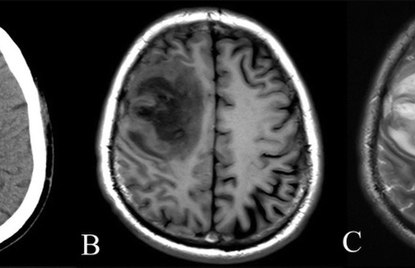

While both CT scans and MRIs have unique benefits, there are significant differences between them. Most notably, a CT scan detects changes and ...